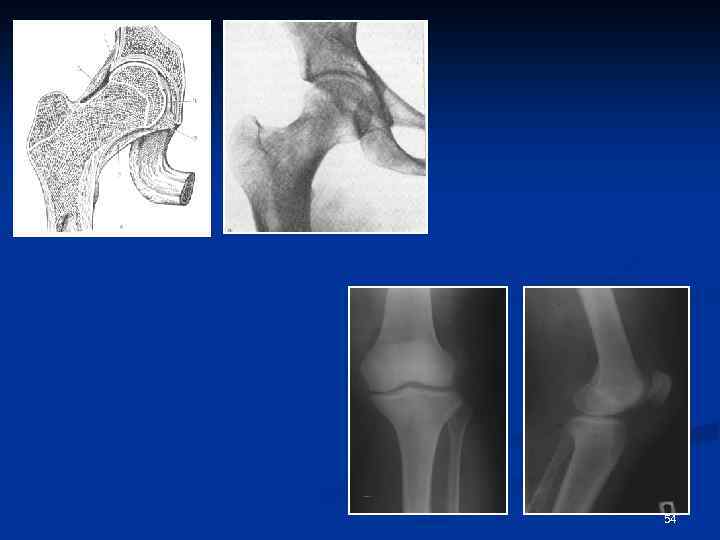

54